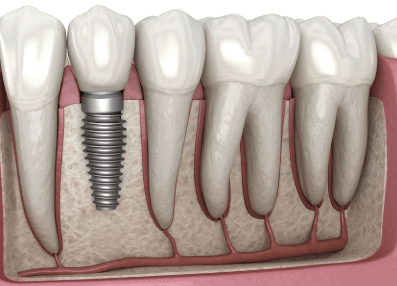

임플란트 시술 후 회복 기간

- 임플란트 시술 후 완전히 정착되기까지 보통 3~6개월이 소요됩니다.

- 1~2주: 잇몸이 아물고 실밥을 제거하는 시기

- 3~6개월: 임플란트가 턱뼈와 완전히 유착됨

- 6개월 후: 보철물(크라운) 장착 후 정상적인 사용 가능

- 환자의 상태에 따라 기간이 달라질 수 있으며, 골이식이 필요한 경우 더 오래 걸릴 수 있습니다.